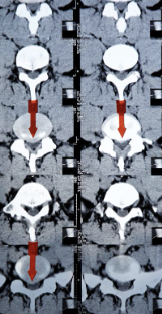

추간판 탈출증 증상 원인 치료방법 등 추간판 탈출증에 대해 정리해드리도록 하겠습니다. 추간판 탈출증은 척추 뼈 사이에 있는 젤리 같은 추간판이 손상되어 신경을 압박하거나 자극하는 질환입니다. 이 질환은 통증, 저림감, 무감각, 근력 저하 등의 증상을 유발할 수 있으며, 특히 요추 부위에서 가장 흔하게 발생합니다. 추간판 탈출증의 원인은 다양하지만, 대부분은 척추의 퇴행성 변화나 반복적인 외상으로 인해 발생합니다. 이 글에서는 추간판 탈출증의 증상과 치료 방법에 대해 알아보겠습니다.

- 무감각: 추간판이 신경을 압박하면, 그 신경이 공급하는 부위에 감각이 없어질 수 있습니다. 이는 심각한 증상으로, 일상 생활에 큰 영향을 미칠 수 있습니다.

- 근력 감소: 추간판이 운동신경을 압박하면, 그 신경이 제어하는 근육의 기능이 저하될 수 있습니다. 이는 근력 저하나 근육 손상으로 나타날 수 있으며, 특히 다리의 근육에서 뚜렷합니다.